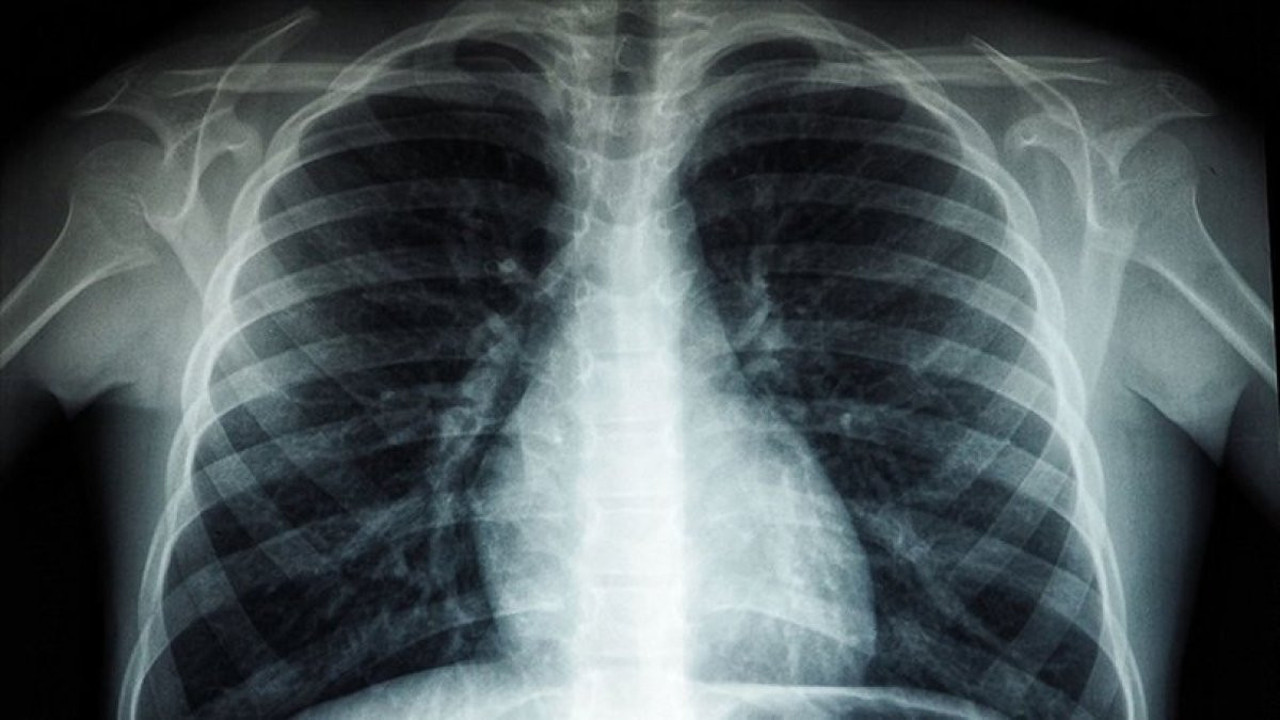

Yapılan bir araştırma, insanların akciğer dokularında küçük plastik parçacıklarının olduğunu ortaya koydu. Prof. Dr. Yıldızeli, solunum ile vücuda giren bu maddelerin, kansere yol açtığını söyledi.

Günlük hayatta sıklıkla kullanılan plastikler, yaşamın her alanında derin yaralar salıyor. İngiltere'de yapılan araştırma, yaşayan insanlardan alınan akciğer dokularında küçük plastik parçacıkları (mikroplastik) tespit edildiğini ortaya koydu. Mikroplastiklerin günlük hayatın her yerinde görüldüğünü belirten Marmara Üniversitesi Pendik Eğitim ve Araştırma Hastanesi Göğüs Cerrahisi Anabilim Dalı'ndan Prof. Dr. Bedrettin Yıldızeli, konuyla ilgili önemli bilgiler verdi. Prof. Dr. Yıldızeli, şunları söyledi:

"Mikroplastik adı verilen polipropilenler günlük hayatımızda her yerde karşılaştığımız plastik maddelerdir. Yemek yediğimiz plastik kaplardan tutun, kullandığımız arabada ve jelatinlerde de görebiliriz. Dolayısıyla günlük hayatımızda bu maddelere çok fazla maruz kalmaktayız. Astım, akciğer hastalığı gibi hastaları tetiklediğini görüyoruz. Hava kirliliğinin yoğun olduğu büyük şehirlerde de görülüyor. Zaten 20 yıl önce ortaya çıkan bazı çalışmalarda akciğer kanseri sebebiyle ameliyat olmuş hastaların akciğer dokularında bu mikroplastik adı verilen yabancı maddeleri görmüştük. Bu maddeler vücudumuza solunum yoluyla girdiğinde yaygın derecede reaksiyon yapmaktadır. Buna bağlı olarak akciğerde kansere kadar yol açabilen çeşitli hastalıklar görmekteyiz. Astım, akciğer hastalığı gibi hastaları tetiklediğini görüyoruz.”

“Özellikle meslek hastalıklarında bu durumu görüyoruz. Hastalarımızda, nefes darlığı, egzersiz kapasitelerinde düşme ve öksürük görülüyor. Bu çalışmayla birlikte meslek hastalığı olmayan bizim gibi normal insanlarda da plastik maddelerin akciğerimize geldiğini gördük. Normalde bir şeyi soluduğumuz vakit bunun akciğerlerimize kaçması ve aşağılara gitmesi mümkün.” diye konuşan Prof. Dr. Yıldızeli sözlerine şunları ekledi:

“Ancak bizim daha aşağıda ufak dediğimiz damarsal düzeydeki yapılarımızda bile mikroplastikler görülebiliyor. Vücut bunu parçalayamadığı için bu kansere kadar yol açar. Mikroplastikler sigara içenler gibi riskli gruptakilerde kanser, astım gibi hastalıklara neden olur. Mikroplastik doğada bozulmaz, yıllarca bozulmadan kalır”